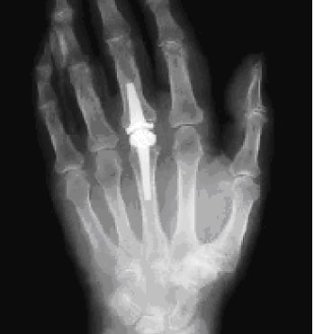

Röntgenaufnahme (Foto: Klinik Bleicherode)

So auch bei Herrn E., der sich mit Beschwerden in einem Fingergrundgelenk in der Rheumasprechstunde der Klinik vorstellte. Alle nichtoperativen Möglichkeiten waren bereits ausgeschöpft, sodass für ihn eine andere Behandlung gefunden werden musste: Im März 2011 ersetzten die Bleicheröder Ärzte daher das Fingergrundgelenk durch ein Kunstgelenk aus Pyrocarbon.

Dass in Bleicherode große Gelenke wie Hüfte und Knie durch Prothesen ersetzt werden – und das in recht großer Anzahl – ist in der Region allgemein bekannt. Aber auch für andere Gelenke gibt es die Möglichkeit des Gelenkersatzes, wenn die nichtoperative Behandlung ausgereizt ist. So auch bei Herrn E., der sich mit Beschwerden in einem Fingergrundgelenk in der Rheumasprechstunde der Klinik vorstellte. Alle nichtoperativen Möglichkeiten waren bereits ausgeschöpft, sodass für ihn eine andere Behandlung gefunden werden musste: Im März 2011 ersetzten die Bleicheröder Ärzte daher das Fingergrundgelenk durch ein Kunstgelenk aus Pyrocarbon.